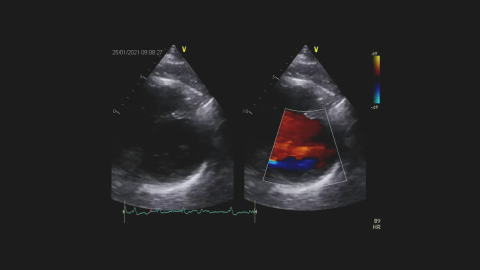

prof. dr hab. n. med. Zbigniew GąsiorPacjentka z ostrym zawałem mięśnia sercowego z uniesieniem odcinka ST.